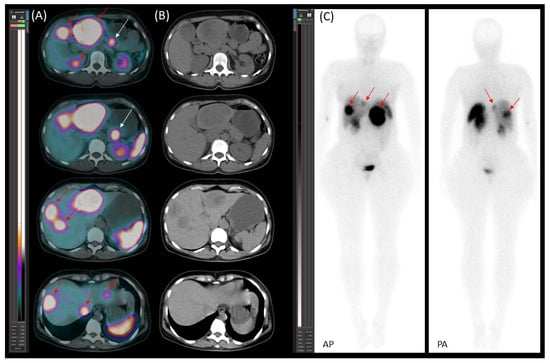

Starting on 21 January 2023, the patient underwent four cycles of [177Lu]Lu-DOTA-TATE therapy due to disease progression despite treatment with somatostatin analogue (SSA). The therapy led to a reduction in both the number and metabolic activity of somatostatin receptor (SSTR)-positive lesions (Figure 8).

Figure 8. [177Lu]Lu-DOTA-TATE therapy response. Transaxial (A,B) SPECT/CT images and planar images (C,D) (AP—anteroposterior; PA—posteroanterior) obtained after the first (A,C) and fourth (B,D) therapy cycles with [177Lu]Lu-DOTA-TATE. The images demonstrate a reduction in both the number and activity of somatostatin receptor (SSTR)-positive lesions in the liver (red arrows), as well as a decrease in the size and activity of a para-aortic lymph node metastasis (blue arrow) following therapy.